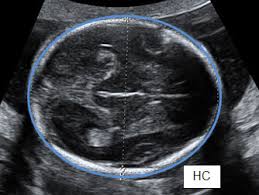

4. HC – Head Circumferences

Diukur luar ke luar